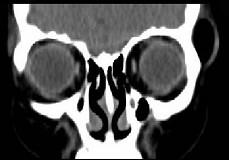

问题 女,31岁,在左眶外上缘发现一包块,质软,余所见无明显异常。如图所示病灶应诊断为 ( )

选项 A、表皮样囊肿 B、淋巴管瘤 C、错构瘤 D、脂肪瘤 E、畸胎瘤

答案 D